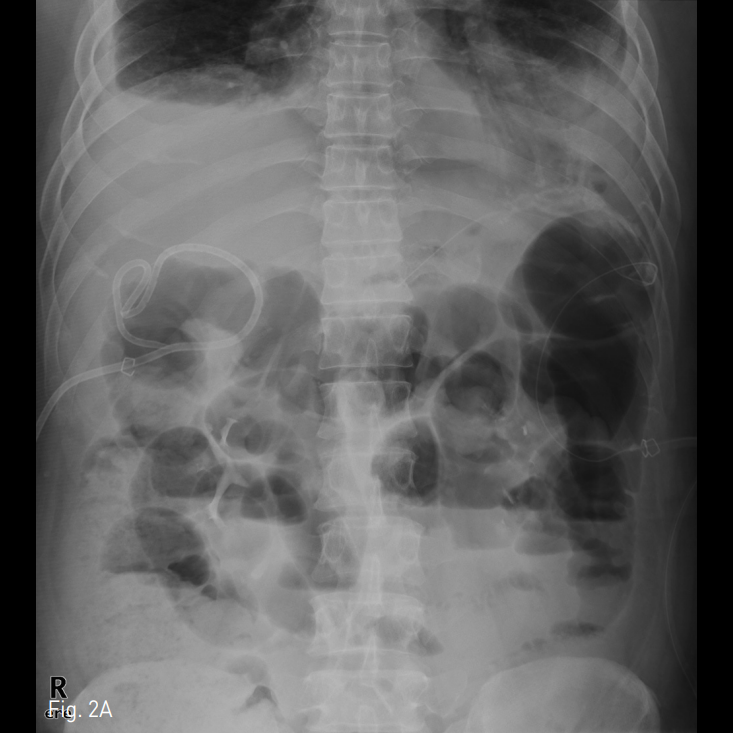

해당 부위 주변으로 Jackson-Pratt관이 거치되어 있으나 효과적인 배액이 안되고 있는 것을 알 수 있으며 복부단순촬영에서 해당 관은 복강 내에서 매우 구불구불한 형태로 보이고 있으며 중간 부위에서는 U자 모양의 회전 부위도 보이고 있어 단순히 유도철사를 이용한 카테터 교환은 어려울 것으로 생각되었음 (Fig. 2).

Fig. 2

A-B. An erect abdominal plain radiograph shows Jackson-Pratt drainage catheter with tortuous passageway including U-turn course (annotated with blue colored line).